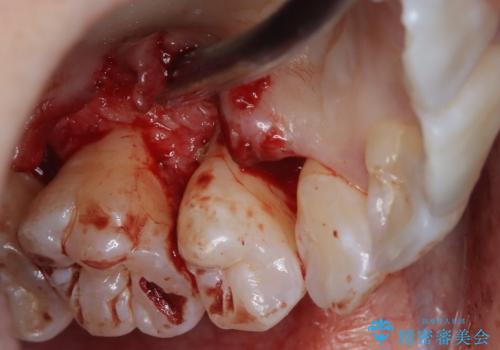

- 定期的にクリーニング(保険適応)に通って頂いている患者さんです。歯周ポケットが4ミリあったため歯茎を開いて歯石を除去するためにオープンフラップ術を行うことにしました。

歯周ポケットがそれほど深くない患者さんでしたが、いざ歯茎を開いてみるとそこにはたくさんの歯石がありました。もし歯周ポケットが4ミリだからと言って放置していれば数年後には、沢山の骨が無くなっていたことが予期出来ます。現段階で歯茎の下にある歯石を除去することにより骨が無くなることを予防する事が出来ました。